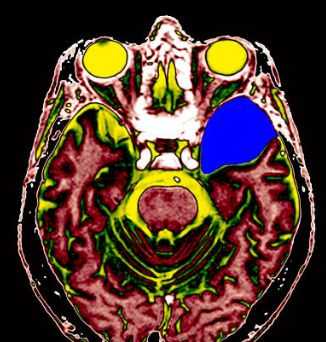

МРТ головного мозга. Т2-взвешенная аксиальная томограмма. Арахноидальная киста. Цветовая обработка изображения.

Арахноидальные кисты представляют собой скопление ликвора между листками расщепленной паутинной оболочки. Арахноидальная киста обычно не сопровождается другими мальформациями. Незначительная часть арахноидальных кист имеет приобретенное происхождение - следствие лептоменингита, операции или кровоизлияния. Частота составляет около 1% от внутричерепных образований. Соотношение полов М:Ж, как 4:1. Типичная локализация - средняя черепная ямка (в области Сильвиевой борозды 50%), межполушарная щель, мосто-мозжечковый угол (11%), за скатом или на уровне четверохолмия (10%), в области червя мозжечка (9%), реже в области межножковой и предмостовой цистерн (3%), а также супраселлярной и хиазмальной цистерн. Ретроцеребеллярная арахноидальная киста довольно часто встречаются за мозжечком и отличима от mega cisterna только по неизменённой задней черепной ямке. Содержимое кисты чисто ликворное, стенки гладкие, чётко очерченные, внутри кисты могут быть перегородки. Мелкие арахноидальные кисты очень трудно увидеть. Меняя ширину окна и его уровень на Т1-взвешенных МРТ изображениях можно заметить, что киста чуть светлее ликвора. Дифференциальная диагностика с эпидермальными кистами лучше осуществляется с помощью МРТ последовательности FLAIR. Эпидермальные кисты становятся яркими, в отличие от гипоинтенсивных арахноидальных.